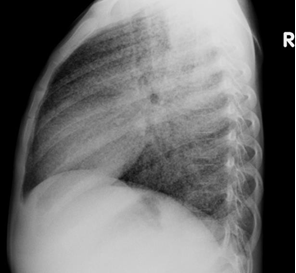

Chest X-ray (CXR): TB enlarged perihilar lymph nodes are better visualised on a lateral CXR than a PA view, therefore, it is important to obtain both PA and lateral films when evaluating a child with suspected TB.